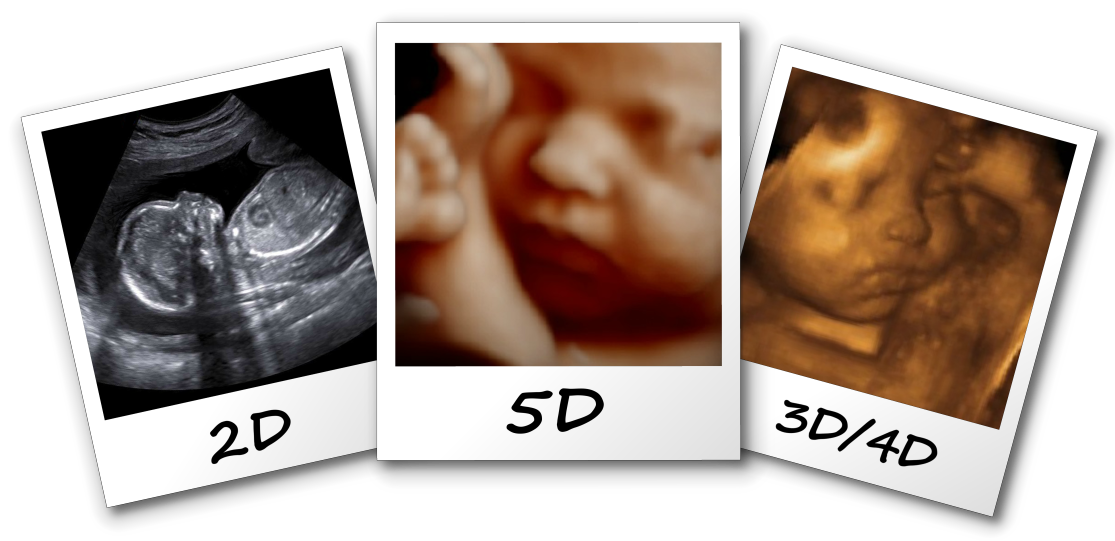

Ultrazvučna dijagnostika Beograd cene, Ultrazvučna dijagnostika u BeograduUltrazvučna dijagnostika Beograd ultrazvuk abdomena Beograd, ultrazvuk štitne žlezde, ultrazvuk prostate, ultrazvuk dojke, ultrazvuk srca, ako ovo tražite i zanima Vas cena ultrazvučnog pregleda i gde u Beogradu može da se uradi eho abdomena i ostala ultrazvučna dijagnostika, ovo je strana za Vas Cena 3D i 4D ultrazvučnih pregleda u Srbiji variraju od 3000 do 8000 dinara, zavisno od grada iz koga ste i od odbrane ginekološke ordinacije Odaberite najbolju ginekološku ordinaciju iz Vašeg grada kako biste imali najprijatnije životno iskustvo koje je pred VamaIako i dalje standardan pregled za analizu razvoja ploda predstavlja 2D ultrazvučni pregled u kome se odgovarajućim presecima po utvrđenom redosledu analizira morfologija ploda, napretkom tehnologije i sofisticiranih kompjuterskih programa, savremenim aparatima se danas dobija kompjuterska animacija izgleda bebe u celini ili njenih određenih struktura u celosti, i ovaj vid generisanja slike se naziva 3D

4D ultrazvuk cena Ekspertski 4D ultrazvuk, uz disk sa snimkom, cene se kreću u rasponu od 3000 do 8400 dinara*Cene su prikazane orijentaciono, za sve precizne i bliže informacije, predlažemo da kontaktirate ordinacije ispod teksta3D / 4D ultrazvuk V průběhu těhotenství získáváme mnoho informací o vývoji a stavu plodu prostřednictvím ultrazvukových vyšetření Základním a současně hlavním ultrazvukovým vyšetřením prenatální péče je 2D ultrazvuk 2D ultrazvuk vytváří obraz na základě dvourozměrného řezu získeného v daném okamžiku z určité pozice ultrazvukové sondyDistribuce tkání a buněk;

3d I 4d Ultrazvuk U Trudnoci U Odnosu Na 2d